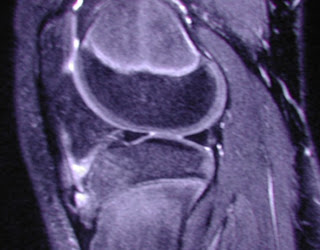

Diagnosis is most often made clinically. When used, radiography shows fragmentation of the tibial tubercle, although this finding alone may represent a normal ossification center. Therefore, the most important diagnostic criteria are seen at MR imaging and include:- soft-tissue swelling anterior to the tibial tuberosity, - loss of the sharp inferior angle of the infrapatellar fat pad and surrounding soft tissues,- thickening and edema of the inferior patellar tendon, and- infrapatellar bursitis.